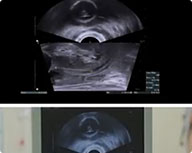

(1)全麻后置入超声探头,横断/矢状面观察前列腺位置大小,并每5mm截图保留;

(5)每组脉冲约 5min,完成后生成治疗报告,结束后每5mm截图;